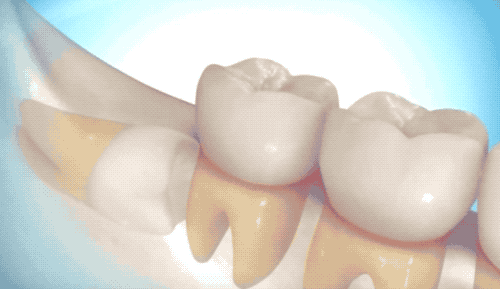

用高速旋轉的渦輪機,把牙齒磨成兩半,依次撬出來。圖示看起來很容易的樣子,但當你聽到鉆機的聲音,你整個人都在小幅顫抖...

露出牙槽骨后,先削除一部分骨頭,露出躺臥如睡美人的橫阻生智齒...如果是已經出肉的智齒,就沒這一步了。

請出那令人聞聲喪膽的牙科渦輪機,先分割智齒,撬出塊頭過大的牙冠來...再把牙根磨切兩半,依次撬出來。當然這樣的操作并不都是必須的,牙醫(yī)會依據(jù)當時的可操作性去處理,畢竟每個哈姆雷特的橫阻生智齒也都可能長得不一樣。